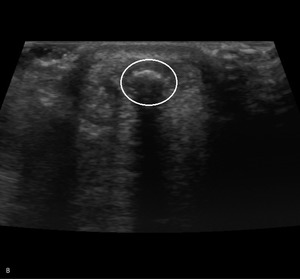

Pacjent, lat 52, zgłosił się do lekarza ortopedy z powodu silnego bólu w okolicy prawej pięty, który wystąpił nagle poprzedniego dnia podczas treningu piłki nożnej. Pacjent uprawia sport regularnie. Do tej pory nie cierpiał z powodu żadnych dolegliwości bólowych tej okolicy, a początek bólu nie był związany z bezpośrednim urazem. Podczas badania stopy okolica ścięgna Achillesa (piętowego) była obrzęknięta i bolesna, ruchy czynne w stawie skokowym znacznie ograniczone. Stwierdzono brak palpacyjnej bolesności w okolicy kostki przyśrodkowej i bocznej z zachowaną stabilnością w ruchach na boki.

Obrzęknięta okolica ścięgna Achillesa wraz z nagłym początkiem dolegliwości wskazuje na jego zerwanie. Niemniej możliwość wykonywania czynnych ruchów w stawie skokowym, nawet w niewielkim zakresie, przemawia za innym rozpoznaniem. Nie występuje też wyczuwalna luka w ścięgnie, jednak może być ona maskowana obrzękiem tej okolicy. Zapalenie kaletki głębokiej ścięgna Achillesa również może wywołać podobne objawy. Często wiąże się ono z występowaniem wyrośli kostnej na kości piętowej (deformacja Haglunda), która drażniąc kaletkę, wywołuje jej stan zapalny. Do złamań zmęczeniowych kości piętowej najczęściej dochodzi u żołnierzy oraz sportowców, którzy biegają długie dystanse po twardym podłożu. Jednakże w tym wypadku jest to mało prawdopodobne rozpoznanie, ponieważ pacjent może stanąć na pięcie oraz nie ma krwiaka i obrzęku tej okolicy.